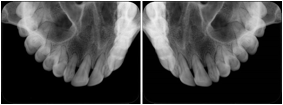

- OO-1. Intra-oral Full Mouth Series Structured Display